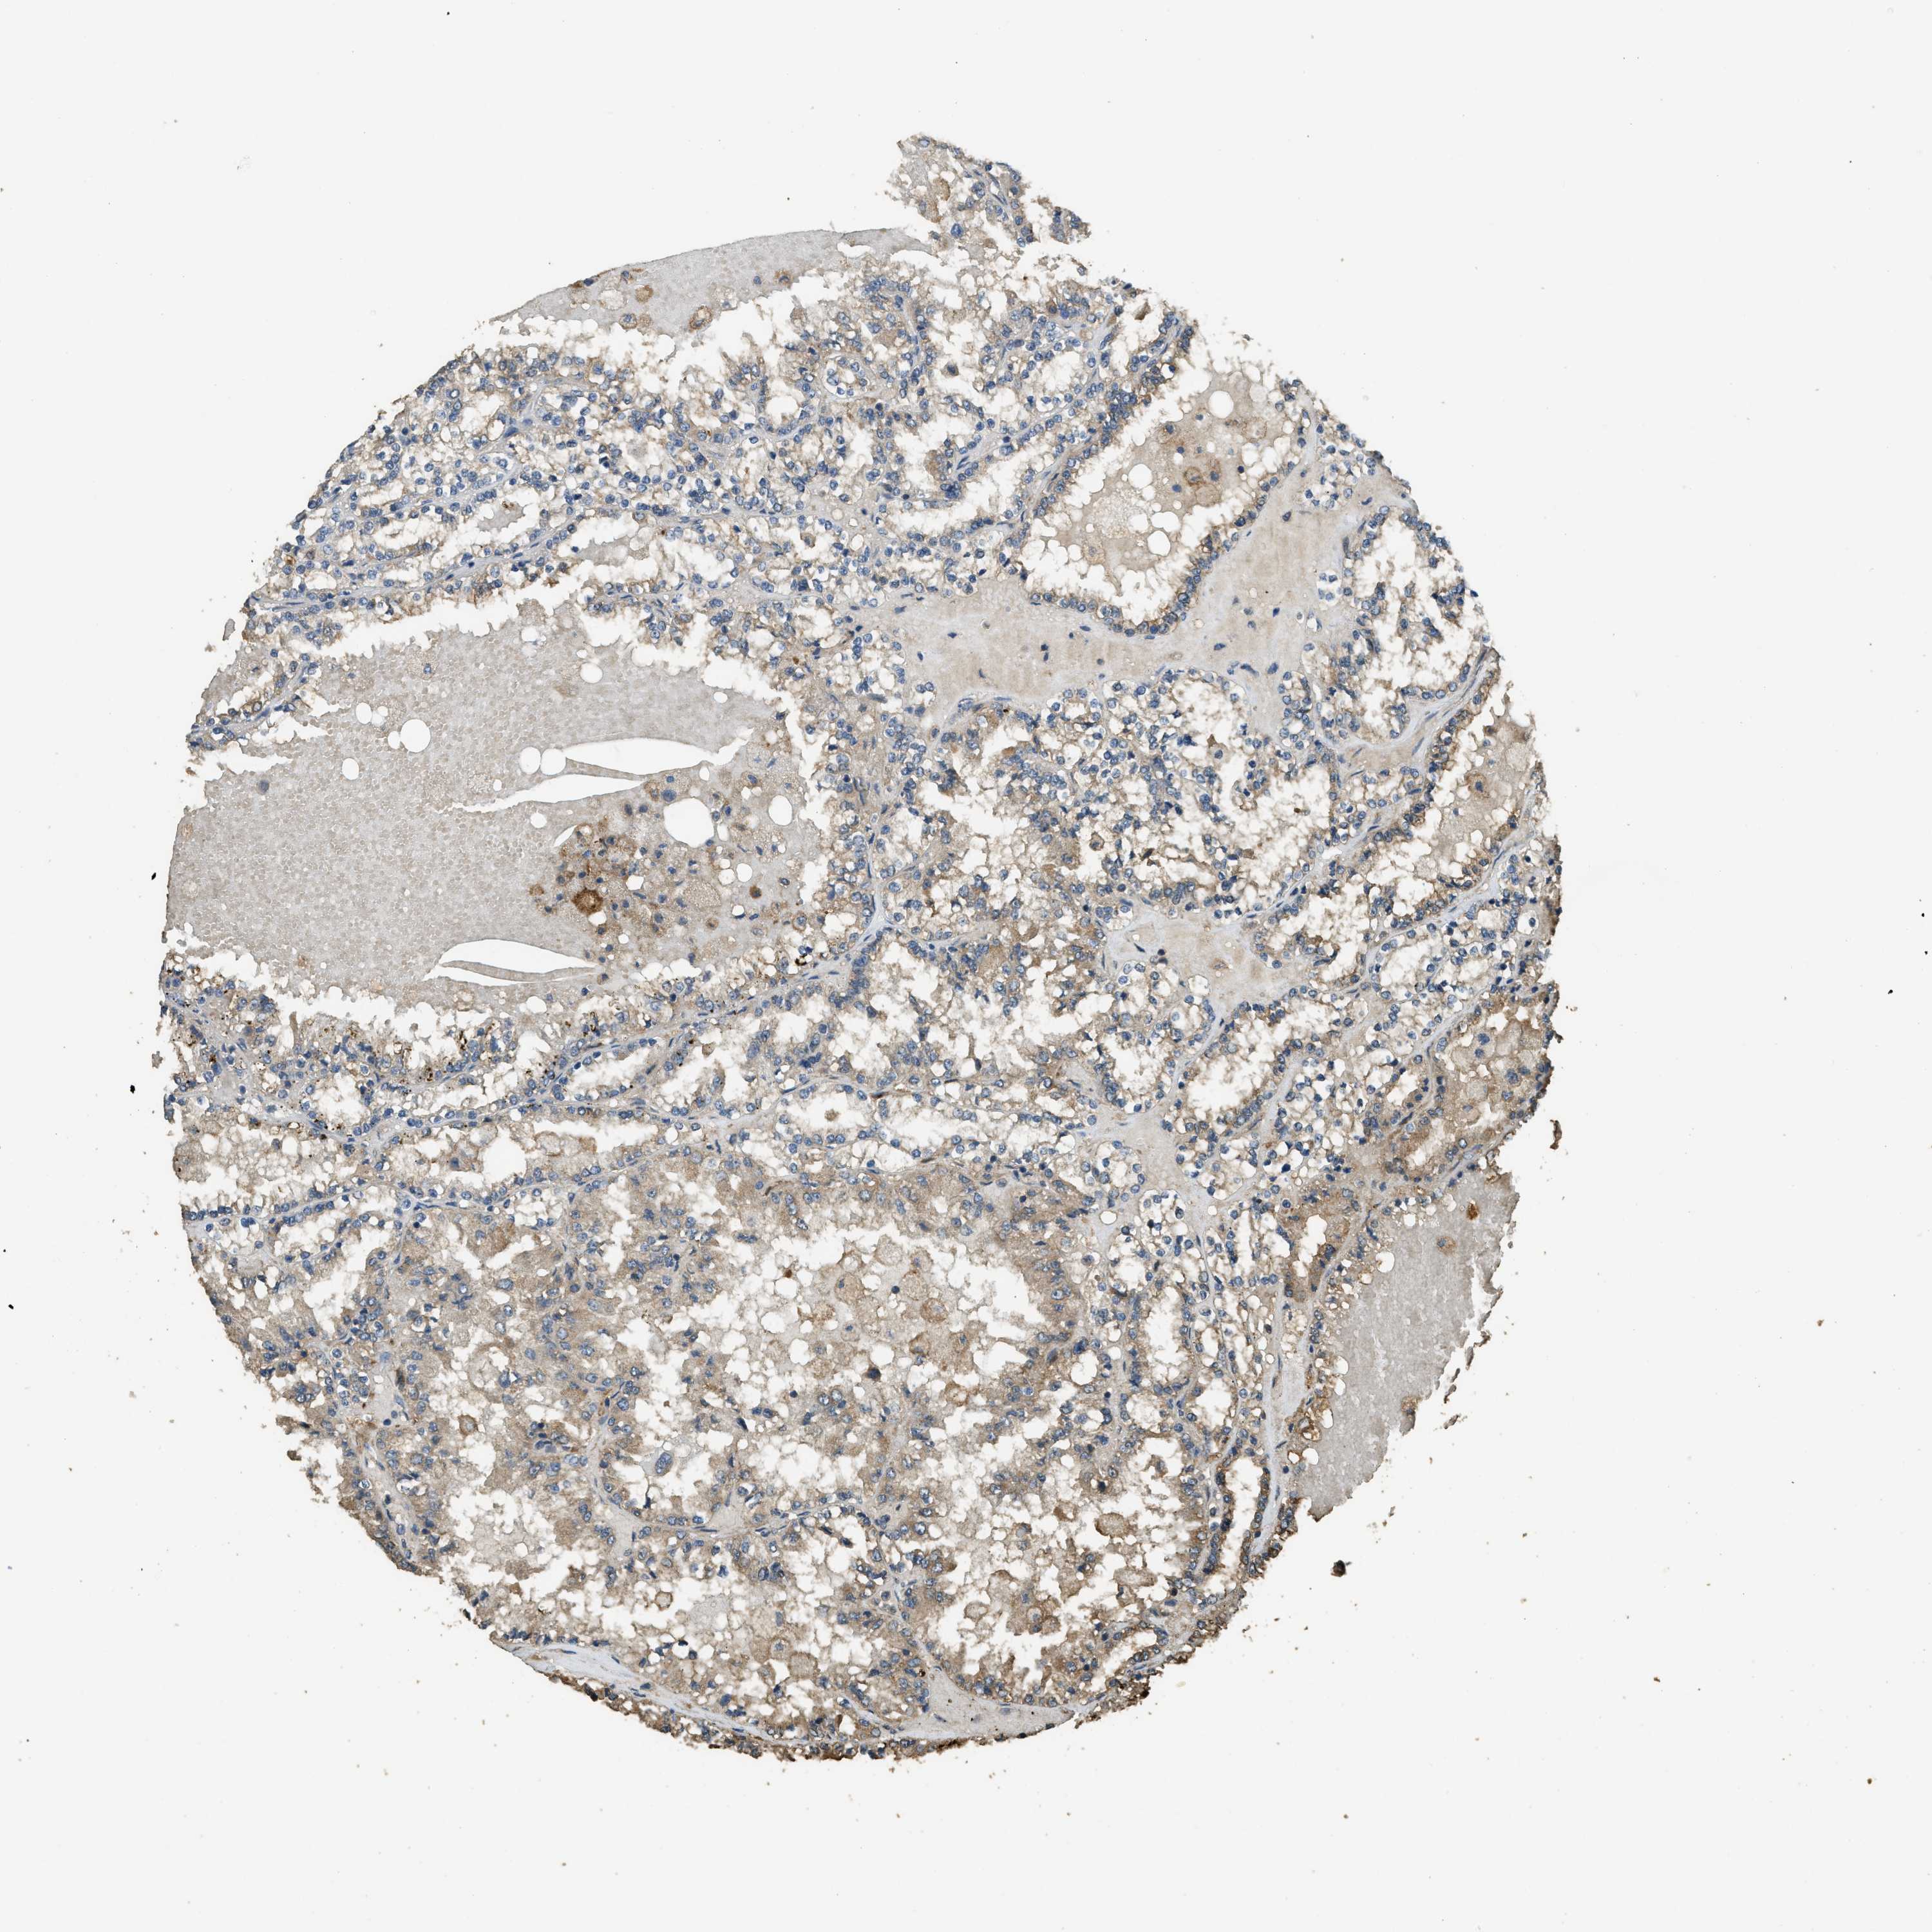

KIDNEY RENAL PAPILLARY CELL CARCINOMA (TCGA) - Interactive survival scatter ploti

The Survival Scatter plot shows the clinical status (i.e. dead or alive) for all individuals in the patient cohort, based on the same data that underlies the corresponding Kaplan-Meier plots. Patients that are alive at last time for follow-up are shown in blue and patients who have died during the study are shown in red.

The x-axis shows the expression levels (FPKM) of the investigated gene in the tumor tissue at the time of diagnosis. The y-axis shows the follow-up time after diagnosis (years). Both axes are complimented with kernel density curves demonstrating the data density over the axes. The top density plot shows the expression levels (FPKM) distribution among dead (red) and alive patients (blue). The right density plot shows the data density of the survived years of dead patients with high and low expression levels respectively, stratified using the cutoff indicated by the vertical dashed line through the Survival Scatter plot. This cutoff is automatically defined based on the FPKM cutoff that minimizes the p-score. The cutoff can be changed by dragging the vertical line or by entering a cutoff value in the square labeled "Current cut-off".

Under the Survival Scatter plot the p-score landscape (black curve; left axis) is shown together with dead median separation (red curve; right axis). Dead median separation is the difference in median mRNA expression between patients who have died with high and low expression, respectively. It is calculated as follows: median FPKM expression of dead patients with high expression - median FPKM expression of dead patients with low expression. This is intended to aid the user in visually exploring custom cutoffs and the associated p-scores and dead median separation.

Individual patient data is displayed and can be filtered by clicking on one or more of the category buttons on the top of the page. Categories describing expression level and patient information include: high, low, alive, dead, female, male and tumor stages. The scale of the x-axis can be toggled between linear and log-scale by clicking on the "x log" button. Mouse-over function shows TCGA ID, patient information and mRNA expression (FPKM) for each patient.

& Survival analysisi

Kaplan-Meier plots summarize results from analysis of correlation between mRNA expression level and patient survival. Patients were divided based on level of expression into one of the two groups "low" (under cut off) or "high" (over cut off). X-axis shows time for survival (years) and y-axis shows the probability of survival, where 1.0 corresponds to 100 percent.

CD276 is not prognostic in Kidney Renal Papillary Cell Carcinoma (TCGA)

Best expression cut offi